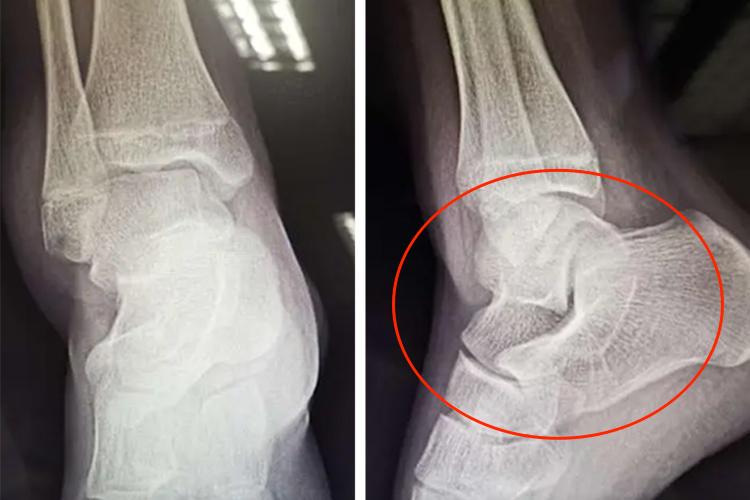

脚踝三角韧带损伤,可出现三角韧带深部中间撕裂圈,并伴随有远端胫腓联合韧带损伤。这是由于内转外伤引起。踝关节内侧图像显示三角韧带表层胫跟部及胫距后部分支部分撕裂。另外,患者还可表现为脚踝疼痛、红肿,并且常伴随脚踝活动障碍。